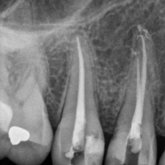

He received his Diploma in Implantology in 2016 from the University of Pretoria, which he passed with Distinction. He is also a member of the International Team for Implantology (ITI), which is based in Switzerland and offers members access to the latest research and cutting-edge techniques.